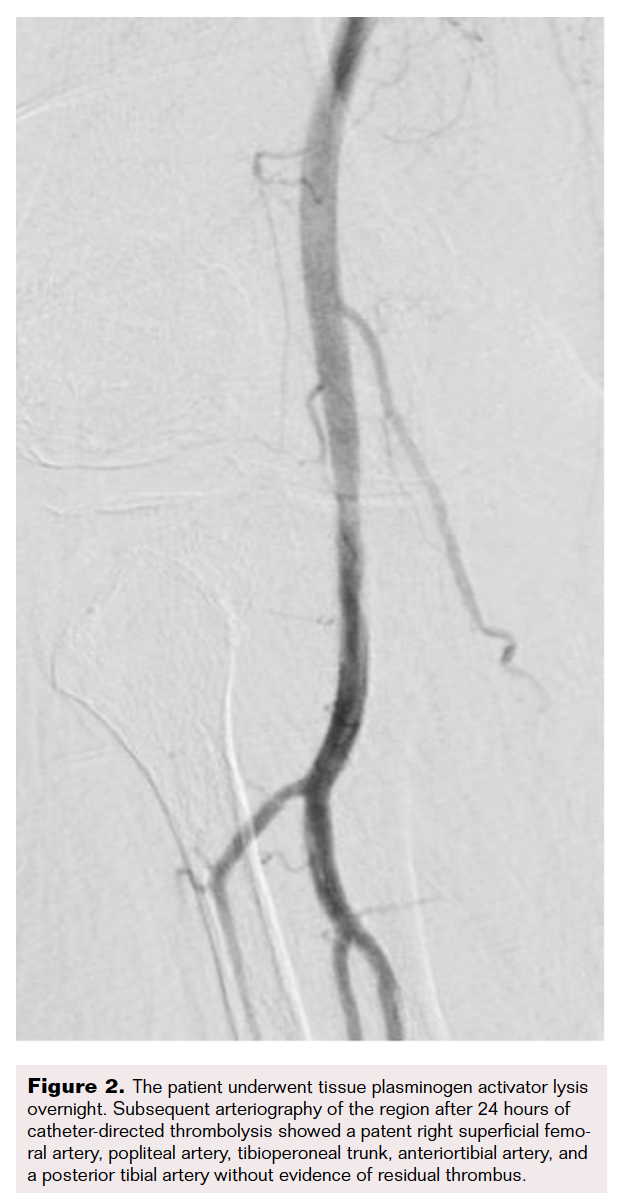

Early recanalization following vessel occlusion has been associated with improved clinical outcomes in ALI. Introducing hybrid therapy with the Indigo system in addition to CDT was intended to improve patient outcomes in a community hospital with a preponderance of high risk vasculopathies (Figure 1 and Figure 2).

Following the start of this initiative, CDT alone was associated with a longer, more tumultuous recovery. Hybrid therapy demonstrated improved clinical outcomes with significant improvements in time until return of pulses and decreased time from procedure to symptom improvement (Figure 3). Although there was a slight improvement in length of hospital stay, it was marginal in comparison; this could be due to confounding factors increasing hospital stay. Factors could include a secondary diagnosis such as pre-existing cardiovascular or cerebrovascular disease, hospital-acquired infection, or placement into rehab.